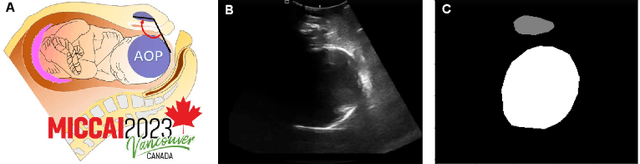

Abstract:Segmentation of the fetal and maternal structures, particularly intrapartum ultrasound imaging as advocated by the International Society of Ultrasound in Obstetrics and Gynecology (ISUOG) for monitoring labor progression, is a crucial first step for quantitative diagnosis and clinical decision-making. This requires specialized analysis by obstetrics professionals, in a task that i) is highly time- and cost-consuming and ii) often yields inconsistent results. The utility of automatic segmentation algorithms for biometry has been proven, though existing results remain suboptimal. To push forward advancements in this area, the Grand Challenge on Pubic Symphysis-Fetal Head Segmentation (PSFHS) was held alongside the 26th International Conference on Medical Image Computing and Computer Assisted Intervention (MICCAI 2023). This challenge aimed to enhance the development of automatic segmentation algorithms at an international scale, providing the largest dataset to date with 5,101 intrapartum ultrasound images collected from two ultrasound machines across three hospitals from two institutions. The scientific community's enthusiastic participation led to the selection of the top 8 out of 179 entries from 193 registrants in the initial phase to proceed to the competition's second stage. These algorithms have elevated the state-of-the-art in automatic PSFHS from intrapartum ultrasound images. A thorough analysis of the results pinpointed ongoing challenges in the field and outlined recommendations for future work. The top solutions and the complete dataset remain publicly available, fostering further advancements in automatic segmentation and biometry for intrapartum ultrasound imaging.

Abstract:In this paper, we propose a method, named BRAU-Net, to solve the pubic symphysis-fetal head segmentation task. The method adopts a U-Net-like pure Transformer architecture with bi-level routing attention and skip connections, which effectively learns local-global semantic information. The proposed BRAU-Net was evaluated on transperineal Ultrasound images dataset from the pubic symphysis-fetal head segmentation and angle of progression (FH-PS-AOP) challenge. The results demonstrate that the proposed BRAU-Net achieves comparable a final score. The codes will be available at https://github.com/Caipengzhou/BRAU-Net.